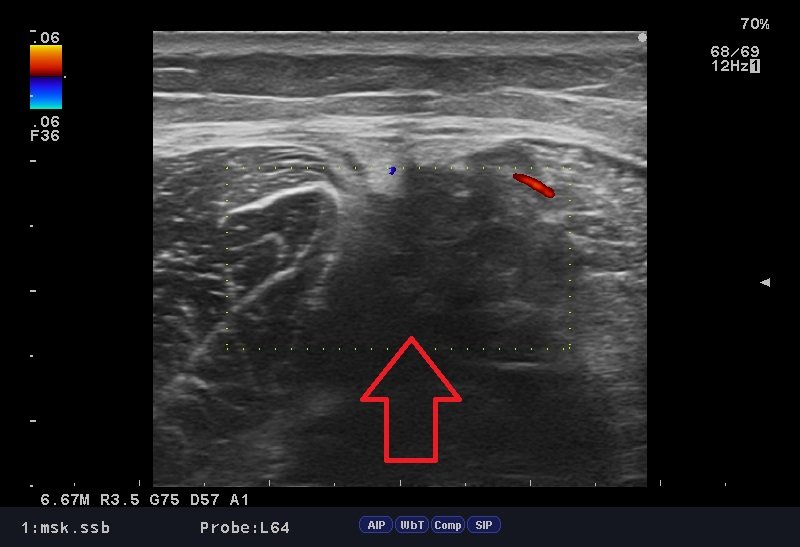

ハムストリングス肉離れ.jpg

「肉ばなれ」はダッシュ時、踏み込み時など、急激に筋肉が収縮する時に、逆の伸張作用(のびる作用)が加わり、筋繊維の一部が切れたり、完全に切れたりすることです。

肉ばなれが発生した時には「バットで叩かれた」「後ろから蹴られた」などと言われる方が多く、「ブチッ」っと大きな衝撃を感じる場合が多々あります。

肉ばなれの原因としては筋疲労・柔軟性の低下・ウォーミングアップ不足が素因となっている場合が多いです。

当院ではしっかり問診、触診、視診、エコー検査を行い、「なぜ今の不調・症状が出ているのか」という、"根本的な原因"を追求し施術を行っております。